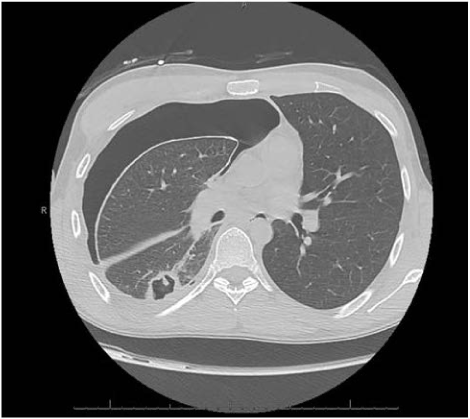

In 2017, a 25-year old Caucasian male with a past medical history of asthma and seasonal allergies presented to an emergency department in Northern Arizona with complaints of 5-6 weeks of progressively worsening dyspnea, with associated productive cough with green-yellow sputum, and fatigue. On the day of presentation, the patient had been moving heavy objects at home, when he developed a sudden worsening of cough, pleuritic chest pain, and thought he had injured his back. He denied fevers, chills, weight loss, diarrhea, rashes, or joint pain. The patient admitted to one day of abdominal upset, with nausea and non-bloody vomiting, about one week prior to admission. In the emergency department, initial vital signs were stable, and labs revealed a CBC with hemoglobin 6.1 g/dL, white blood cell count of 11.9 × 103/µL, platelets 357 × 103/µL, with a differential of 31% lymphocytes, 53% neutrophils, 6% monocytes, and 7% eosinophils. C-reactive protein was 5.9 mg/L and complete metabolic panel was within normal range. Initial chest x-ray showed a large right pneumothorax and right pleural effusion, requiring emergent chest tube placement (Figure 1). Follow-up CT scan of the chest with contrast showed improvement of pneumothorax and pleural effusion but revealed a thick-walled 3.9 cm cavitary mass in the right lower lobe with satellite nodules, which were concerning for an infectious process (Figure 2). Physical exam after chest tube placement was grossly benign, except for noted white purulent drainage from the tube. Social history was significant for recent travel to northern Mexico and Jamaica (at age 18). The patient was admitted to the ICU for spontaneous pneumothorax and a cavitary lung lesion with suspected infectious etiology, and empirically started on broad-spectrum antibiotics with piperacillin-tazobactam and clindamycin.

Figure 1. Chest X-ray demonstrating large right pneumothorax and a cavitary lesion

Figure 2. CT chest without contrast demonstrating a right lower lobe cavitary lesion